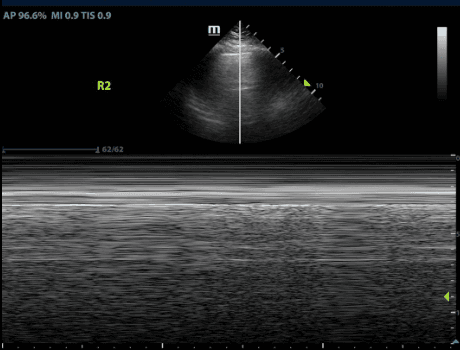

The most specific sign of a pneumothorax is the presence of a lung point. This marks the transition from normal lung sliding to absent lung sliding. Thus it marks the boundary between the collapsed and non-collapsed lung.

M-mode, or Motion mode, is a type of ultrasound modality that displays motion of a structure through time. See our post on Lung Sliding for more information on using M-mode to diagnose a pneumothorax.

Being highly specific for pneumothorax, the lung point delineates the border of the collapsed lung and allows for determining the actual size of the condition. Remarkably specific for pneumothorax, it precisely outlines the border of the collapsed lung. Clinically, the distance is often assessed laterally between the sternum and the lung point, with larger pneumothoraces exhibiting a more lateral and posterior lung point.